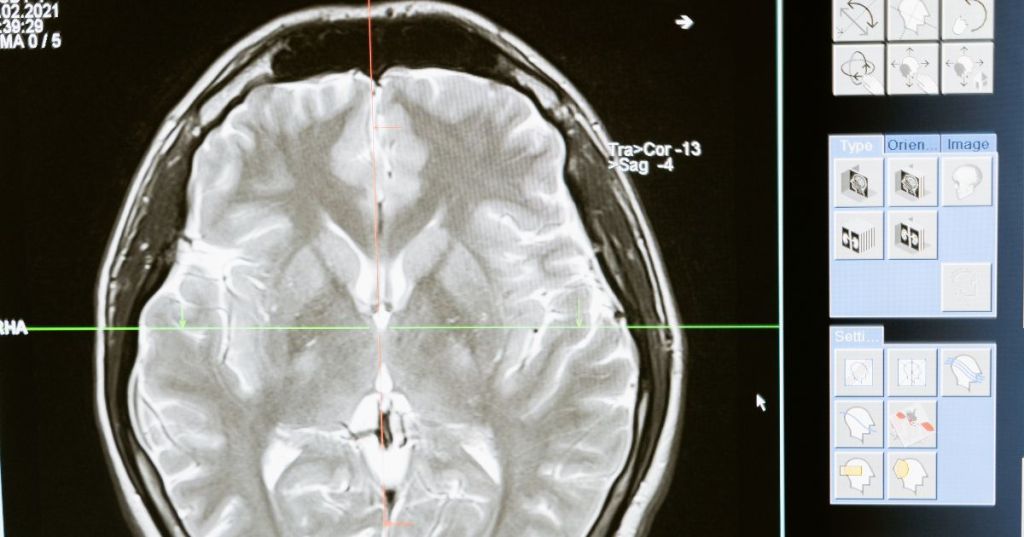

However, advanced neurological care is often expensive. From MRI scans to brain surgeries, treatment costs can reach several lakhs of rupees. For many families, this makes access to neuro healthcare nearly impossible without financial support. This is where the Chief Minister’s Comprehensive Health Insurance Scheme (CMCHIS) plays a game-changing role. Under CMCHIS, eligible families in Tamil Nadu — including residents of Chennai, can avail free treatment for complex neurological conditions at some of the city’s leading hospitals.

Neurological care often involves advanced diagnostics, surgeries, and long rehabilitation programs. Some of the treatments covered under CMCHIS include:

| MRI Brain Scan | 10,000 – 18,000 | Free under CMCHIS |